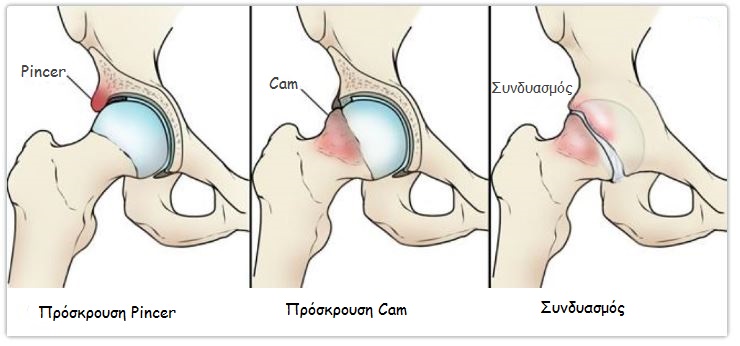

Μηροκοτυλιαία πρόσκρουση: Ταξινόμηση

Υπάρχουν 3 τύποι:

- Pincer: στον τύπο αυτό η πρόσκρουση γίνεται λόγω ανώμαλης οστικής προεξοχής στην πλευρά της κοτύλης.

- Cam: η οστική προεξοχή βρίσκεται στην πλευρά της μηριαίας κεφαλής, κυρίως στο πρόσθιο τμήμα της, στο όριο κεφαλής και αυχένα. Διαταράσσεται έτσι η φυσιολογική σφαιρικότητα της κεφαλής.

- Συνδυασμός και των δύο (Τύπος Pincer-Cam): συνυπάρχει το πλεονάζον οστούν τόσο στην κοτύλη, όσο και στο μηριαίο.